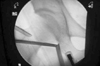

Fig. 3

Serial fluoroscopic images of classic portal insertion method in central compartment. (A) Vacuum seal shadow due to the negative intracapsular pressure is created by distraction of the joint. (B) The needle is inserted and the stylus is removed, then break the seal (C) as in air arthrogram, confirm the lateral labral silhouette. (D) The cannula/obturator assembly is being passed over the guide wire that had been placed through the spinal needle. (E) Then anterior portal is made.